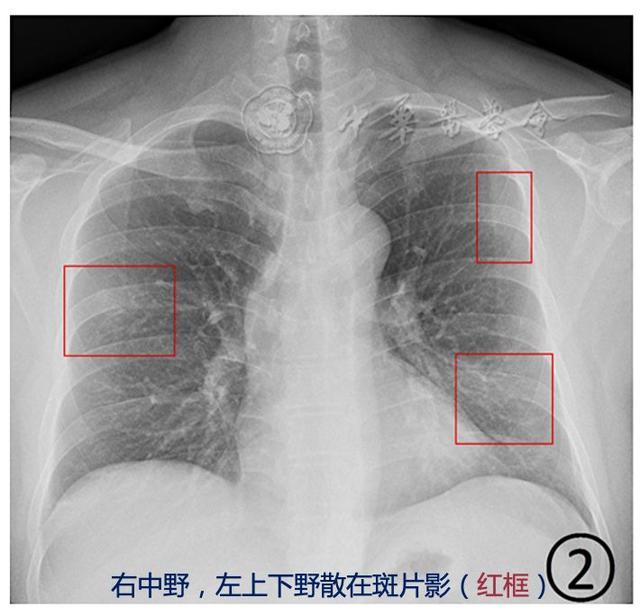

体检查出“肺结节”怎么办?如果有这些特征,很可能是肺癌来临肺结节是指在肺部发现的一个小的、局部增生的病变。许多人在体检中偶尔发现肺结节后会感到担忧,尤其是在不了解病理机制的情况下。肺结... 肺结节的大小、形状、边缘、密度等特征是判断是否恶性的关键。一般来说,如果结节较大( 3cm)、边缘不规则、密度较高、出现钙化或分叶状...

肺结节必知!3种常见类型及应对方法,看完就能用!实性肺结节 实性肺结节就像是肺里出现的一个“小实心球”,在CT图像上表现为密度较高的结节。这种结节有可能是良性的炎症留下的痕迹,也... 看看这“小实心球”到底是啥来头。这就好比你发现家里有个不明物体,得仔细瞧瞧是不是危险物品。记住,实性肺结节不一定就是大麻烦,但定...